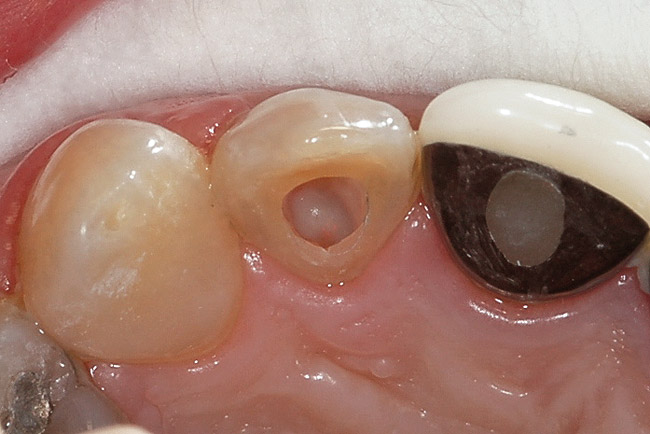

Pulp necrosis as evidenced by periapical radiolucency is an infrequent sequela to PCO occurring in approxi­mately 7% to 16% of cases; consequently, prophylactic endodontic therapy is not recommended by most authors.28,39-41 Teeth with PCO likely have diminished healing capacity, and it is not well established whether a secondary trauma or additional dental treatment causes necrosis. In some instances, such as preparing a tooth with PCO for an abutment, it may be prudent to perform prophylactic endodontic therapy before the definitive restorative procedure. A recent article by daCunha and colleagues suggests implementing endodontic therapy prior to development of a periapical radiolucency in a tooth with PCO, based on two major considerations: (1) the technical difficulty and complications that may occur in treating these teeth; and (2) their review of a study that demonstrated a 97.9% success rate for teeth treated without periapical radiolucencies vs a 62.5% success rate for teeth treated with periapical radiolucencies.42 Specific clinical situations will dictate clinical decisions; however, given the relatively low incidence of pulp necrosis in teeth with PCO, endodontic treatment usually is not recommended in the absence of a periapical radiolucency or symptoms. Nonetheless, if a periapical lesion develops, endodontic therapy can be both challenging and fraught with complications (Figure 4). The use of operatory microscopes in the hands of a skilled clinician is warranted and improves the chances of a successful outcome.

Figure 4  Endodontic therapy was attempted on a tooth with calcific metamorphosis, with subsequent perforation and file fracture in the PDL.

Figure 4